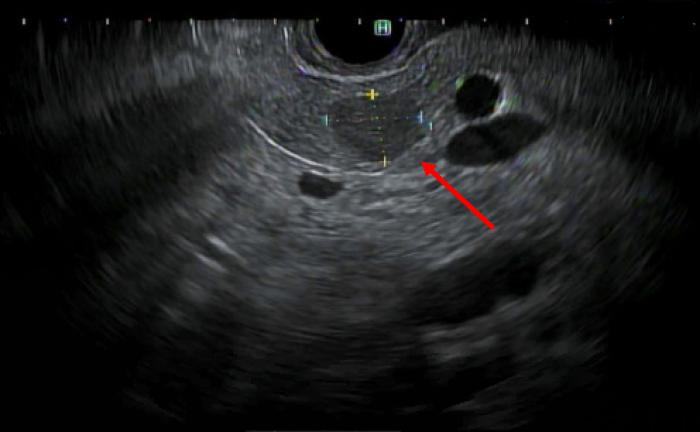

Liver parenchyma that resides outside of the normal hepatic confines is defined as accessory liver if in communication with the native biliary tree, or ectopic liver (EL) if it is not. EL can develop in a variety of tissues, including but not limited to the gallbladder, the hepatic ligaments, the pancreas, and retroperitoneum. EL has an increased propensity for malignant degeneration resulting in hepatocellular carcinoma (HCC). A 67-year-old Korean male presented with epigastric discomfort and was found to have an elevation in his transaminases. Cross-sectional imaging demonstrated a 1.3 cm solid mass in the body of the pancreas with features concerning for either a pancreatic ductal adenocarcinoma or pancreatic neuroendocrine tumor. Subsequent endoscopic ultrasound and fine needle aspiration demonstrated cells of epithelial origin with hepatocellular differentiation. A robotic-assisted distal pancreatectomy and splenectomy was performed with final pathology demonstrating a well-differentiated HCC. EL with malignant degeneration resulting in HCC requires surgical excision. The majority of patients reported with EL resulting in HCC in the pancreas have had the tumors located in the body and tail. Therefore, definitive treatment requires distal pancreatectomy and splenectomy. Herein, we describe the presentation, workup, and definitive treatment of HCC arising in the pancreas.

位于正常肝脏边界之外的肝实质,如果与天然胆管树相通,则定义为副肝;如果不相通,则定义为异位肝(EL)。EL可发生于多种组织,包括但不限于胆囊、肝韧带、胰腺和腹膜后。EL发生恶性变导致肝细胞癌(HCC)的倾向增加。一名67岁的韩国男性因上腹部不适就诊,发现转氨酶升高。横断面成像显示胰腺体部有一个1.3厘米的实性肿块,其特征提示为胰腺导管腺癌或胰腺神经内分泌肿瘤。随后的内镜超声和细针穿刺显示为具有肝细胞分化的上皮来源细胞。行机器人辅助远端胰腺切除术和脾切除术,最终病理显示为高分化HCC。发生恶性变导致HCC的EL需要手术切除。大多数报道的胰腺EL导致HCC的患者,肿瘤位于体部和尾部。因此,明确的治疗需要远端胰腺切除术和脾切除术。在此,我们描述了胰腺HCC的临床表现、检查和明确治疗。